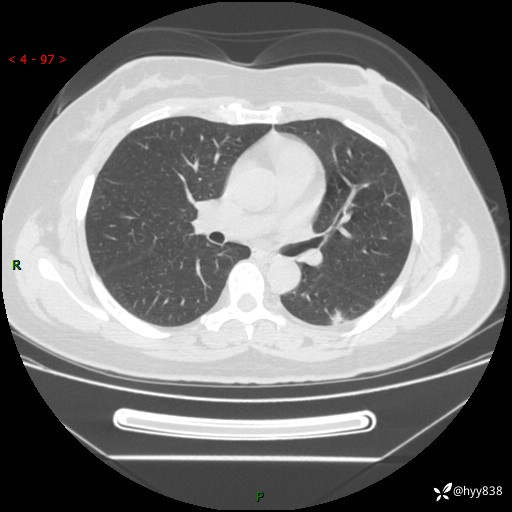

胸部CT平扫(2023.3)